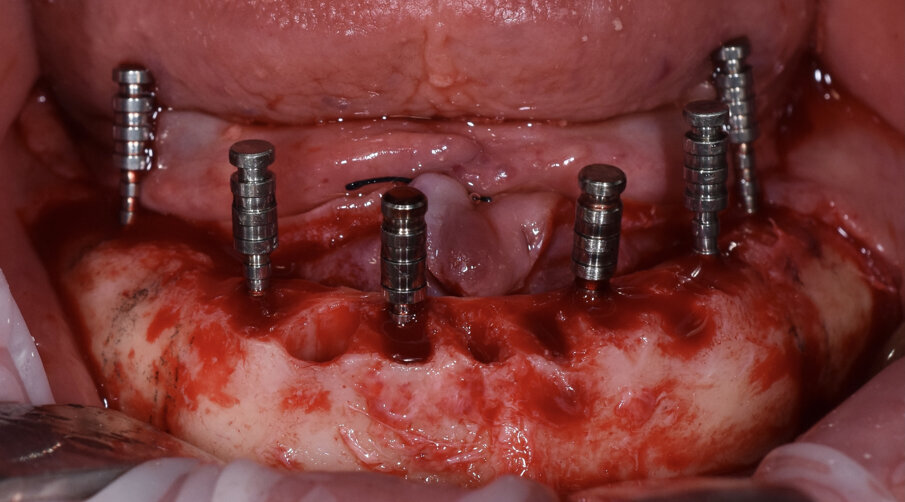

Paziente di sesso maschile di 73 anni, con anamnesi negativa per patologie di rilievo. All’esame clinico e radiografico si evidenzia nell’arcata inferiore la presenza di residui radicolari a supporto di un vecchio ponte, con attacchi per la stabilizzazione di una protesi scheletrata di tipo mobile. Prima di procedere alla fase chirurgica e di rimuovere lo scheletrito viene eseguita un impronta digitale con scanner (3Shape) in modo da registrare la dimensione verticale che verrà utilizzata come riferimento per la realizzazione del carico immediato. In sedazione cosciente e previa terapia antibiotica si procede alla rimozione dei residui radicolari, quindi si esegue una generosa osteotomia e si procede al posizionamento di numero 6 impianti assiali (AB Dental device) a esagono interno. Si esegue quindi la sutura dei lembi con vicryl 4/0 e si procede alla prese dell’impronta digitale utilizzando gli scan body come transfer (Figg. 1-11). I file in STL vengono inviati al laboratorio per la realizzazione della protesi provvisoria a carico immediato. Si applicano quindi le viti di guarigione. Dopo 72 ore si procede alla consegna del provvisorio che rimarrà in bocca per 4 mesi in attesa dell’osteointegrazione (Figg. 12-23).

Fig. 9 - Scan body per impronta digitale.

Fig. 10 - Visione occlusale.